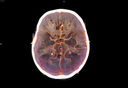

A new software helps radiologists view, analyze, and evaluate brain images.

In Greece, as in other countries, there is an increase of neurodegenerative diseases, predominantly Alzheimer’s Disease – mainly because of the aging population.[1] Although it is the neurologist who is responsible for the diagnosis, radiology is playing an increasingly important role. This is manifest in the work of radiologist Andreas Papadopoulos, MD, PhD, scientific coordinator at Iatropolis Medical Group, who has come to appreciate the benefits of artificial intelligence.

For the first time, data is provided in a structured way, allowing a comparison.